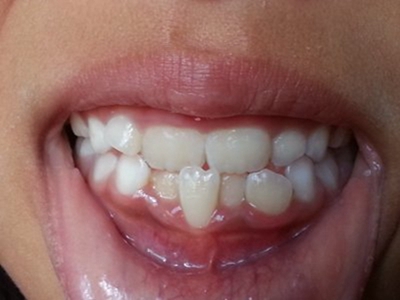

阻生牙是指由于邻牙、骨或软组织的阻碍而只能部分萌出或完全不能萌出,且以后也不能萌出的牙。引起牙阻生的成因,主要是由于颌骨缺乏足够的空间容纳全部恒牙。常见的阻生牙为下颌第三磨牙、上颌第三磨牙及上颌尖牙。

阻生牙可反复引起冠周炎,或引起邻牙牙根吸收和破坏,位置不正,不能完全萌出,好发部位是上、下颌第三磨牙。